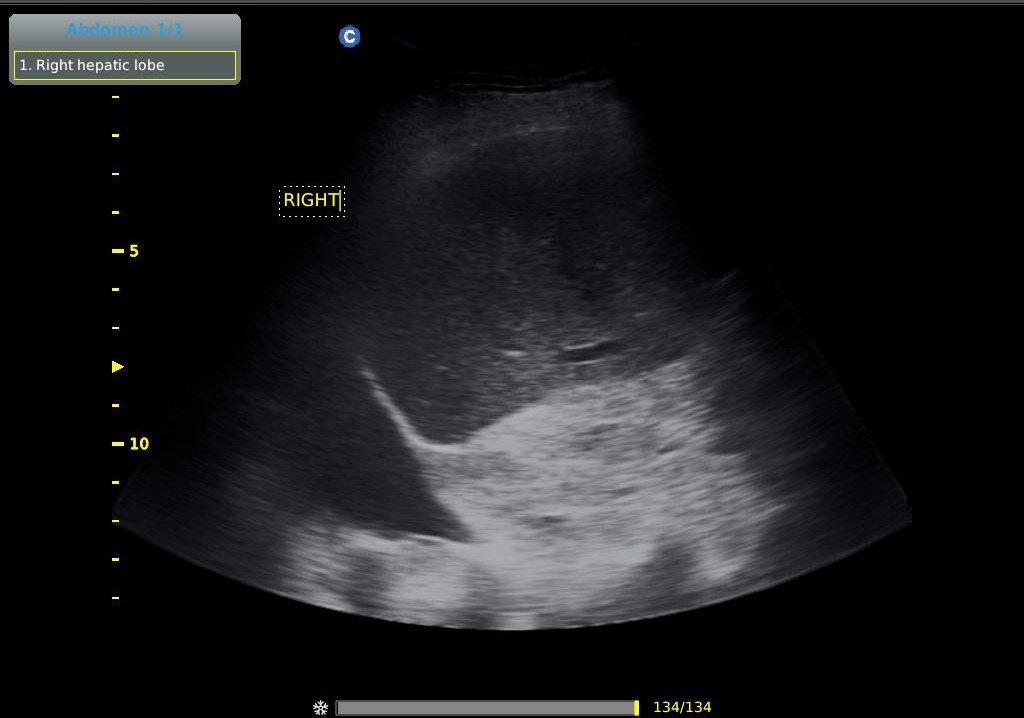

- Υπέρηχος άνω κοιλίας κατ’ οίκον ( ήπαρ, χοληδόχος κύστη, χοληφόρα, πάγκρεας, σπλην, νεφροί )

- Υπέρηχος άνω και κάτω κοιλίας κατ’ οίκον σε άντρα ( ήπαρ, χοληδόχος κύστη, χοληφόρα, πάγκρεας, σπλην, νεφροί, ουροδόχος κύστη, προστάτης)

- Υπέρηχος άνω και κάτω κοιλίας κατ’ οίκον σε γυναίκα ( ήπαρ, χοληδόχος κύστη, χοληφόρα, πάγκρεας, σπλην, νεφροί, ουροδόχος κύστη, μήτρα, ωοθήκες)